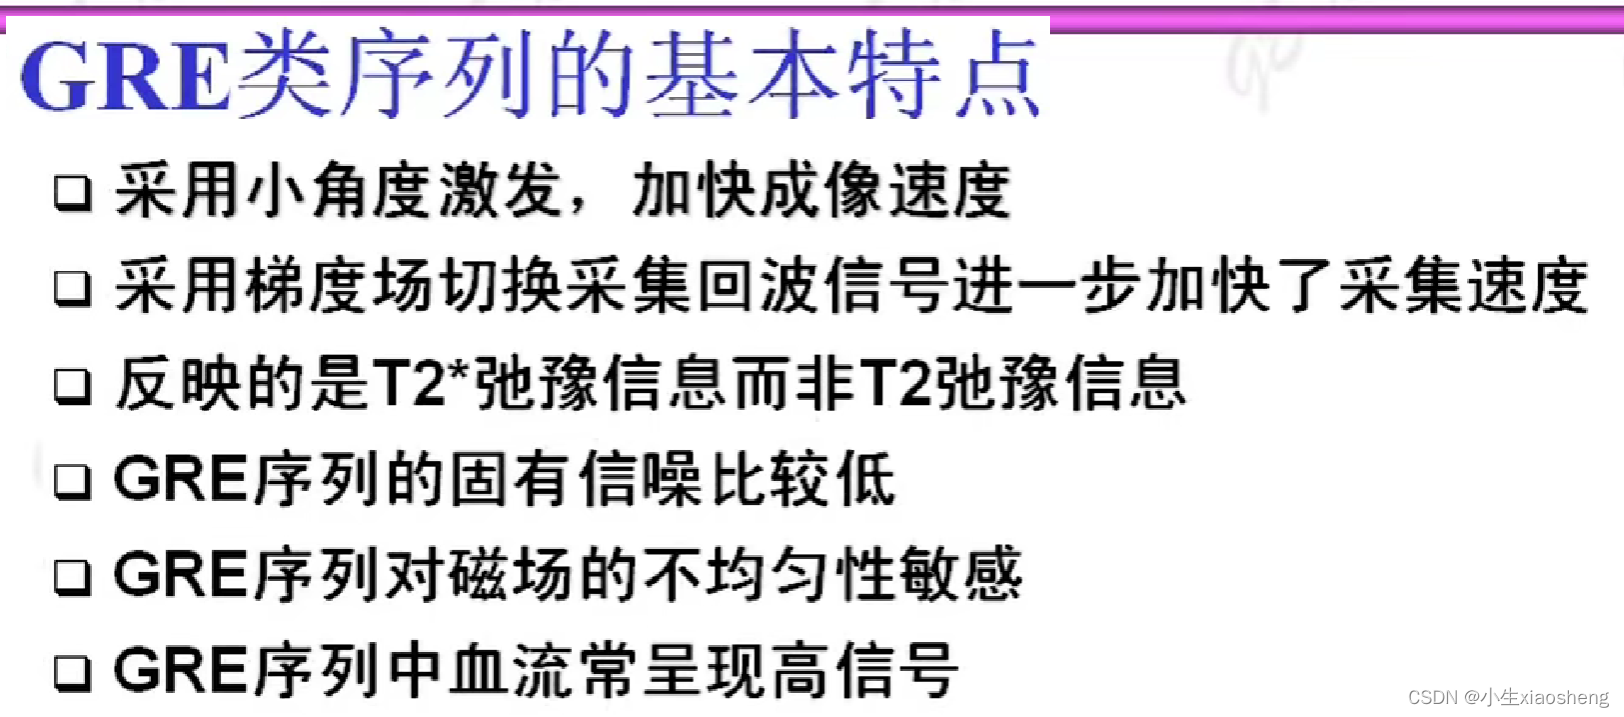

五、梯度回波类序列

GRE就是梯度回波

GRE序列中的稳态:流入的和流出的量是一样的,那么容器中的数据一直都是一样的。

1.扰相梯度回波GRE

在SSFP成像中,如果每个SSFP-REF能够保持稳态,那么就可以利用这些回波信号来重建高质量的MRI图像。然而,由于各种因素的影响(如磁场不均匀性、组织特性等),SSFP-REF可能会发生变化,这可能会导致图像伪影(如带状伪影)的出现。而扰相主要用于提高成像速度和消除图像伪影。扰相技术的主要目的是在前一次射频脉冲(α脉冲)的MR信号采集后,对组织中的质子群的相位进行干扰,使其失相位加快,从而消除残留的横向磁化矢量。

扰相梯度回波序列(Spoiled GRE)中的扰相技术可以有效地消除由于组织T2值大于TR时间而造成的图像的带状伪影。此外,扰相GRE序列还具有较高的空间分辨率和较短的扫描时间。